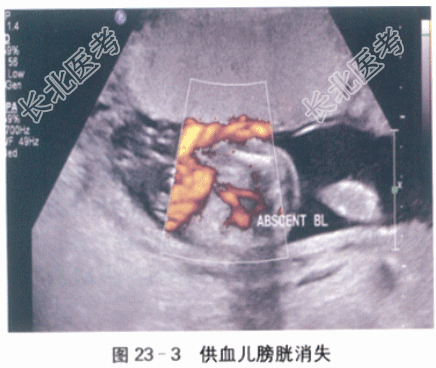

- [材料题] 患者,女性,32岁,已婚,因“G₂P₀,停经22周,腹胀一周”入院。初潮15岁,月经5天/30天,无痛经。末次月经2021-4-13。停经35天查尿HCG(+),孕产期2022-1-20。停经10周当地医院超声提示双胎妊娠。唐氏筛查未做。在当地医院每月做一次超声。于1月前(孕18周)在当地医院行超声检查未提示异常。近一周,自觉腹胀严重,平卧睡后有胸闷不适主诉。随即到当地妇幼保健院行超声检查:宫内两个胎儿,羊水多,羊水指数360mm。当地医院拟诊“孕22周,双胎妊娠,羊水过多”,建议转至上级医院诊治。既往体健,除人工流产外,无其他手术和外伤史,家族无遗传病及肿瘤病史,无双胎家族史。0-0-1-0,3年前自然流产一次。体格检查:Wt72kg,Ht159cm,BP130mmHg/80mmHg,HR100次/min,一般情况良好,内科检查无异常,全身浅表淋巴结未及肿大,腹隆,无压痛,下肢水肿(++)。腹部张力高,可见腹壁浅静脉怒张。产科检查:腹围122cm,宫高35cm,胎心140/152次/min,胎位不清。骨盆外测量无异常。实验室和影像学检查:血常规检查:Hb107g/L,RBC4.2×10¹²/L,WBC3.7×10⁹/L,N71%,PLT121×10⁹/L。凝血功能检查:APTT32s,PT12s。肝肾功能检查:AST23μmol/L,ALT35μmol/L,TP60g/L,Alb31g/L,TB10μmol/L,BUN5.6mmol/L,Cr90μmol/L。肝炎指标及HIV,RPR:均阴性。超声检查:2021-7-8外院B超图片提示一个孕囊,两个胚芽。入院后B超检查:胎盘后壁。宫内可见两个胎儿,大胎儿体重位于该孕周第52百分位,羊水深度18.3cm,心胸比增大(59%),静脉导管血流A波反流(见图23-1),脐血流舒张期倒置,大胎儿出现水肿和腹腔积液(见图23-2)。小胎儿体重位于该孕周第9百分位,羊水过少(深度0.9cm),呈包裹趋势,膀胱消失(见图23-3)。脐血流、大脑中动脉血流、静脉导管多普勒血流无异常。两胎儿体重相差26%。宫颈长度37mm。